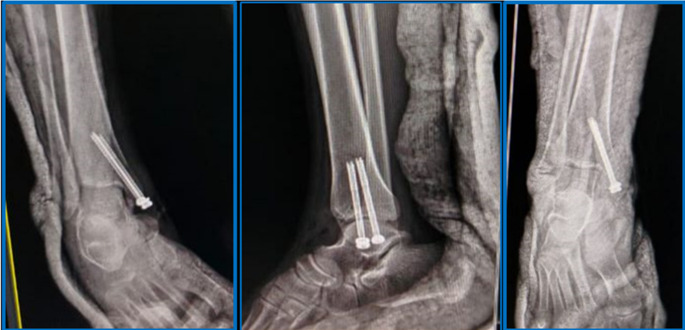

Materials and methods: A prospective randomized controlled clinical trial (RCT) was conducted on 50 patients with isolated displaced MM fractures, treated with CRPF (group A) or ORIF (group B), at orthopaedics department of university hospital, from April 2021 to April 2023. Fractures were classified by Herscovici classification. The primary outcomes were incidence of complications and time to union based on radiographic assessment by plain radiographs of ankle. The secondary outcomes were functional assessment by Foot and Ankle Ability Measure (FAAM) for activities of daily living (ADLs) and sports, American Orthopaedic Foot and Ankle Society (AOFAS) score, and VAS.

Results: No significant differences were noticed among two groups regarding age, sex, side affected, mechanism of injury, smoking, Herscovici classification, or follow-up duration. Mean final FAAM-ADLs was 97.6 ± 2 in group A, and 95 ± 3.4 in group B, (P = 0.155). Mean final FAAM-sports was 87 ± 11.4 in group A, and 73.4 ± 15.6 in group B, (P = 0.312). Mean final AOFAS score was 95.9 ± 8.4 in group A, and 94.6 ± 9.5 in group B, (P = 0.237). Mean final VAS for pain was 0.9 ± 0.5in group A, and 1.5 ± 0.9 in group B, (P = 0.453). Mean time of solid radiographic union was 9.5 ± 2 weeks in group A, and 10.4 ± 3 weeks in group B, (P = 0.026).

Conclusion: CRPF of displaced isolated MM fractures is an efficient method with comparable radiographic and functional outcomes to ORIF. Based on these results, percutaneous fixation could be a good alternative for managing displaced isolated MM fractures.